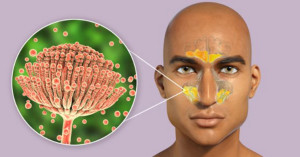

Viêm xoang do nấm, còn được gọi là viêm xoang nấm, là một tình trạng viêm nhiễm xoang dưới tác động của các loại nấm.